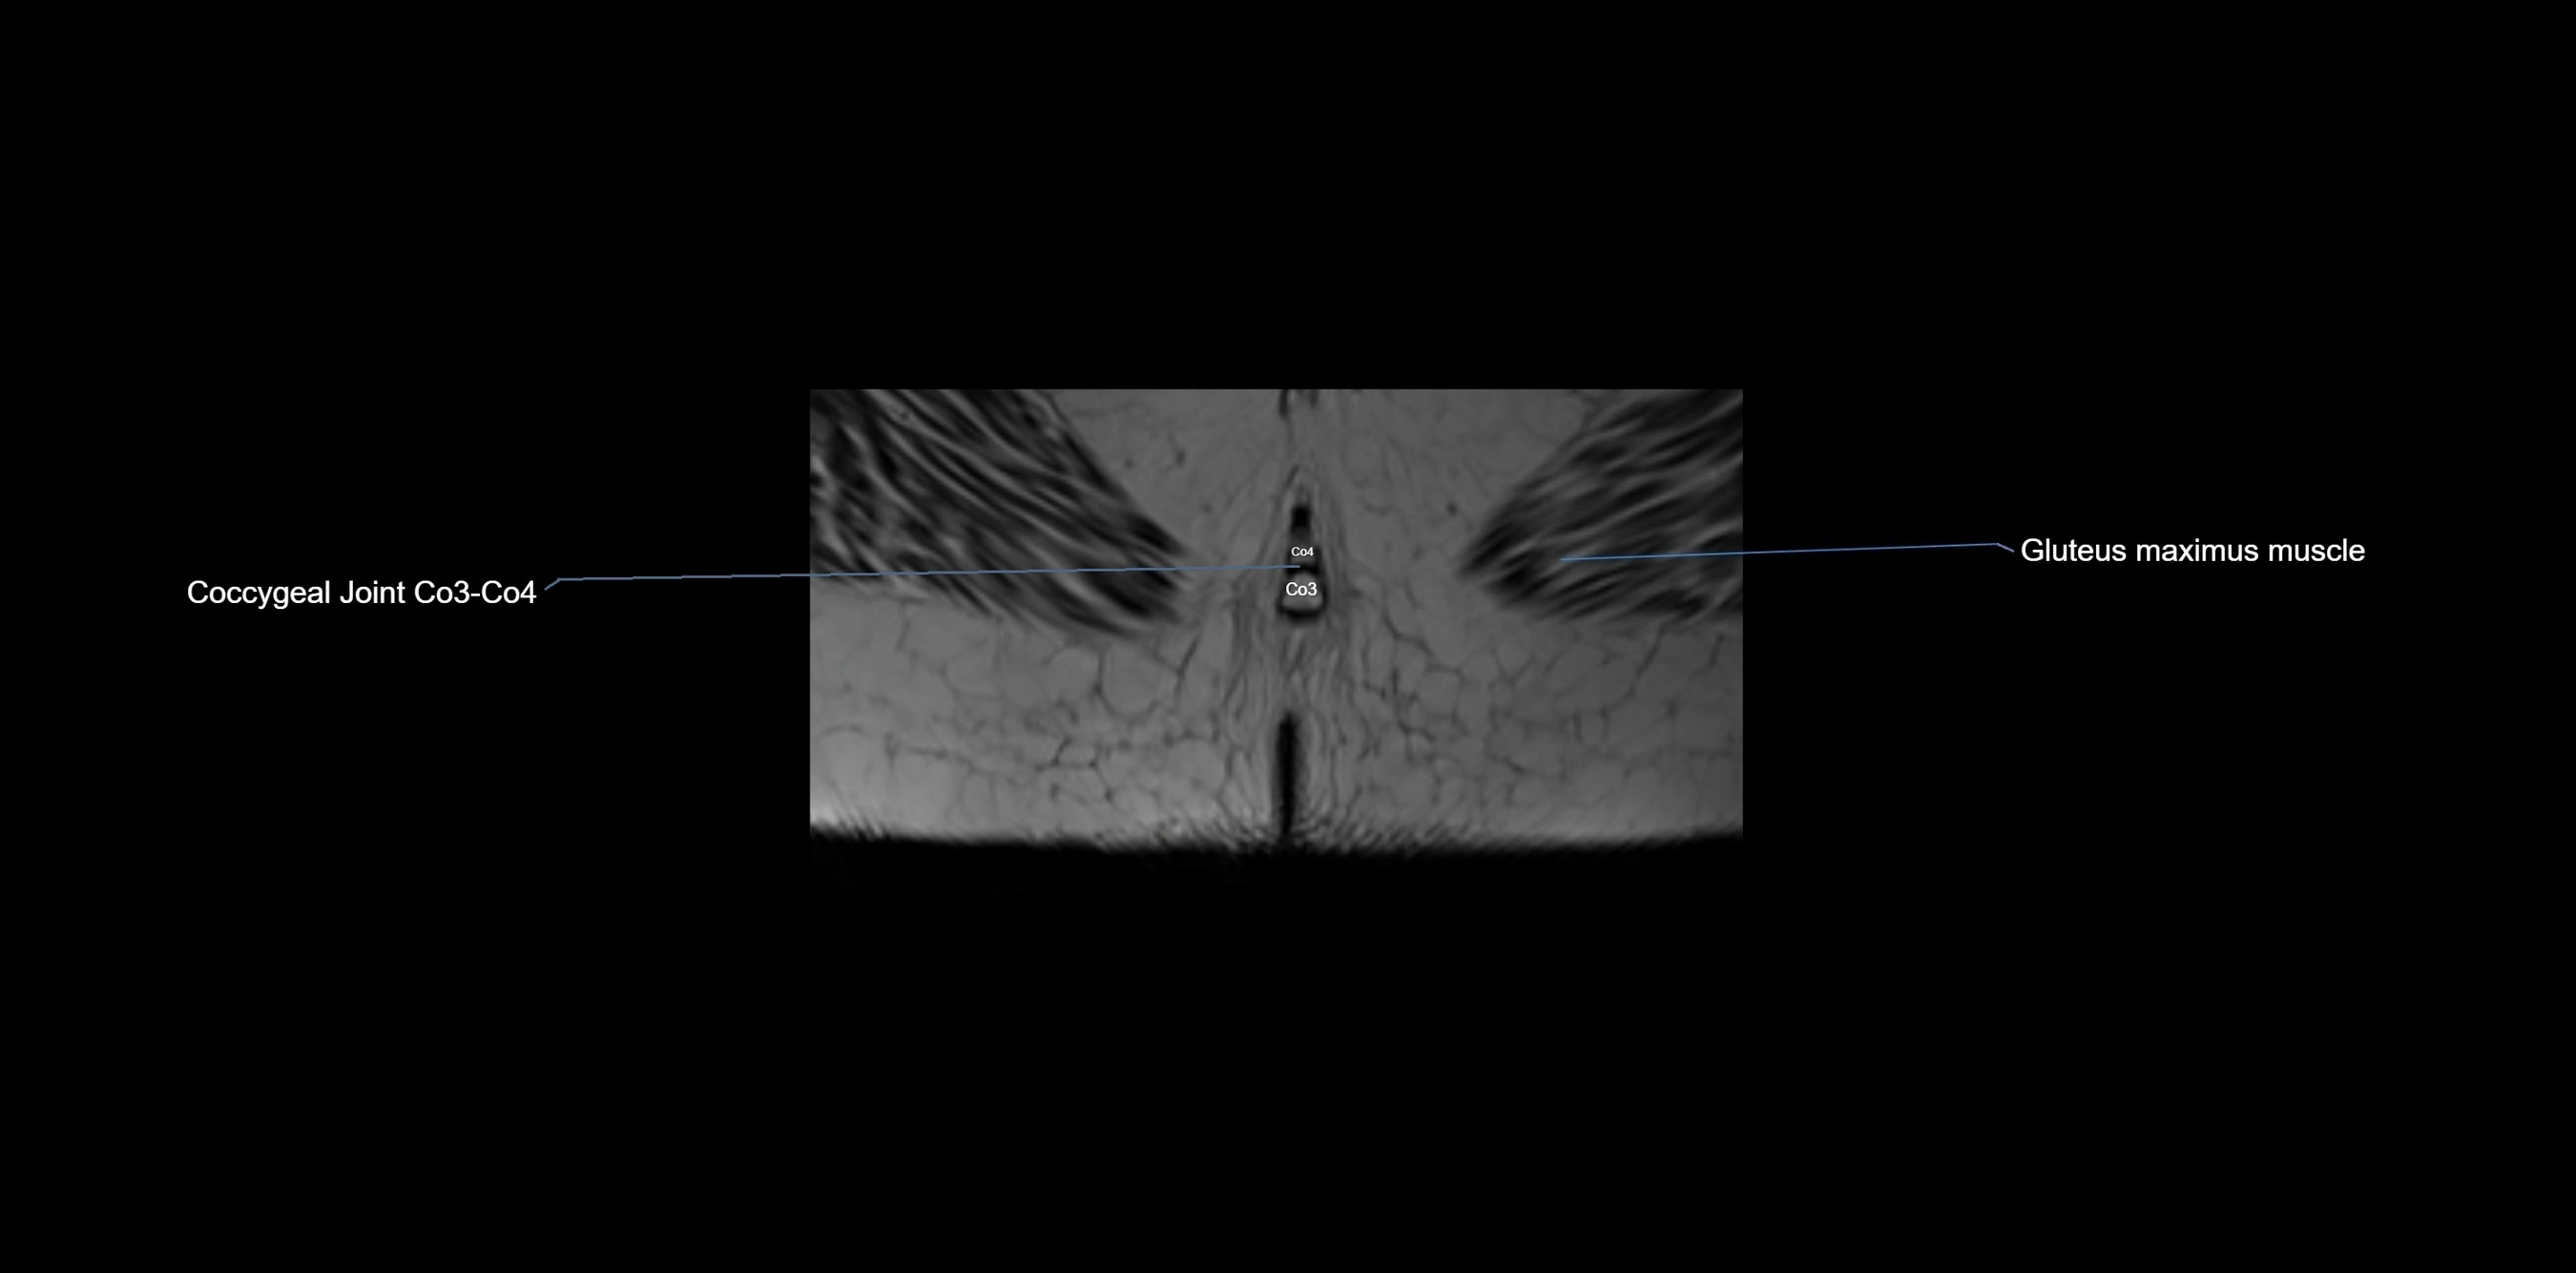

CT image

image

CT VRT image